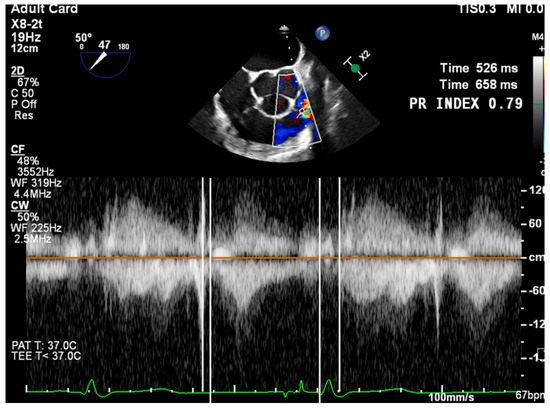

- PR Jet Width/RVOT Width: With >65% consistent with severe PR (Figure 3).